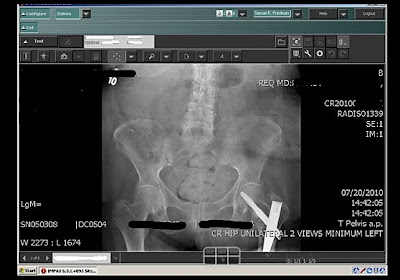

ResolutionMD Mobile (imagem abaixo) roda em um servidor OEM e é acessado por rede Wireless, permite pesquisar em qualquer PACS conectado e exibe qualquer imagem DICOM. Mas o que você vê não é armazenada no IPAD, portanto os problemas com privacidade dos dados dos pacientes são minimizados.

![]() |

| ResolutionMD Mobile |